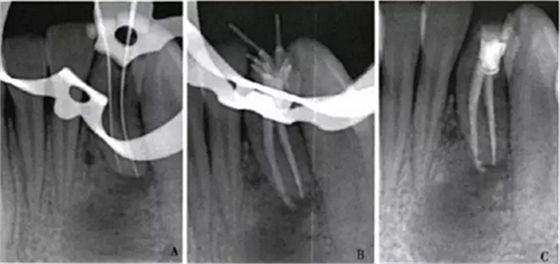

1周后,患者述疼痛消失。復(fù)診采用冷測(cè)壓方法根管充填(圖2),牙冠開髓孔處應(yīng)用Chem—flex(DentsplyDeTreyGmbH,Konstanz,Germany)充填。由于患牙牙冠形態(tài)異常,且唇側(cè)形態(tài)尚未恢復(fù);患牙周圍有牙石、軟垢,建議患者行牙周及修復(fù)治療以維持長期療效,被患者拒絕。9個(gè)月后隨訪,患者自述患牙經(jīng)治療后無癥狀,臨床檢查見32叩診正常,無松動(dòng);影像學(xué)檢查見32根尖周圍透射區(qū)域明顯減?。▓D3)。

A:32術(shù)中片確定根管工作長度;B、C:32術(shù)后片示根管充填適充

圖2 32根管治療x線片